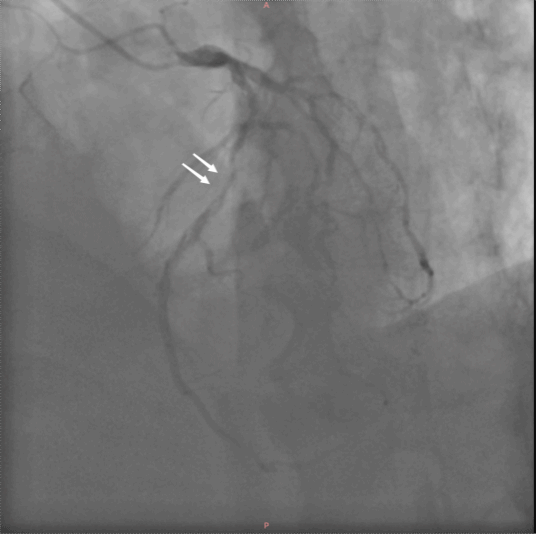

两个月前,老王心梗发作,冠脉造影发现,原先前降支的支架内出现了严重狭窄。

左图:术前冠脉造影(白色箭头指示前降支支架内严重狭窄) 右图:术前CT影像(双肺肺气肿、肺大疱)